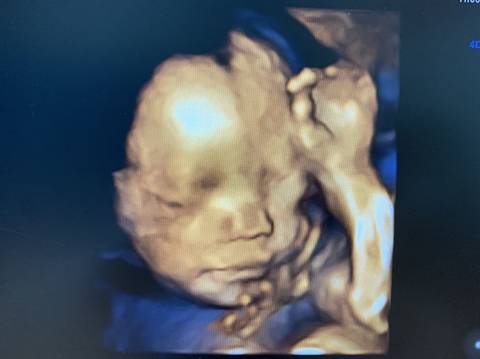

你好。我们是判断不了男宝宝跟女宝宝的,孕期定期检查,我觉得宝宝健康就好的。祝心想事成 。

你好,对于宝宝是男孩女孩虽然很好奇,但是怀孕的单子、数据、表现是判断不出来的,在这也愿你心想事成。

亲爱的,通过这些判断不出来是什么样性别的哈,反正宝宝发育好就是最好的哈,祝你好孕。

通过这些是看不出来的,而且也不准确,在怀孕期间,我觉得只要宝宝发育好的话,还是不要想太多了,男孩女孩都一样的。